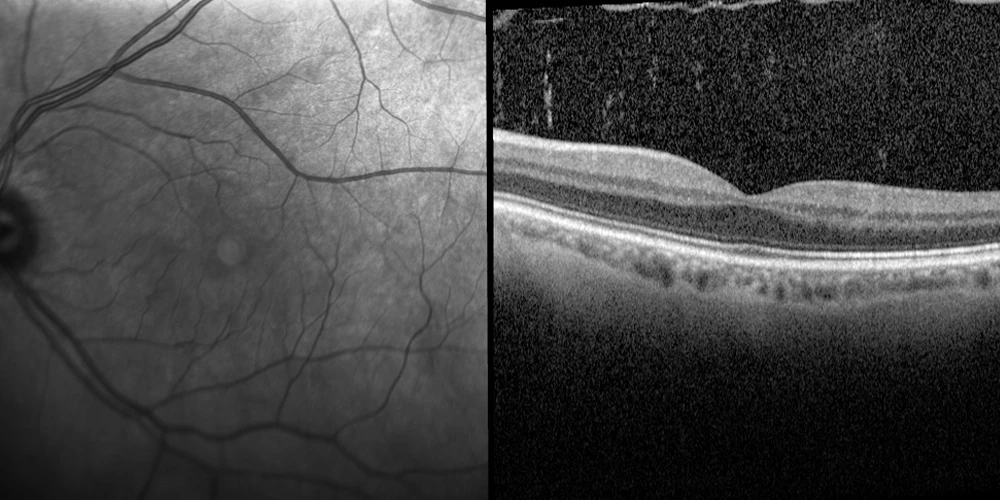

Posterior Vitreous Detachment

The inside of the eye is filled with a gel like substance which helps maintain its shape, known as the vitreous.

The vitreous attaches onto the surface of the retina through millions of fine fibres. As we age the vitreous begins to shrink and slowly pulls away off the retina. Sometimes the fibres break, allowing the vitreous to detach and shrink from the retina. In most cases a vitreous detachment, also known as a posterior vitreous detachment, is not sight-threatening and requires no treatment.